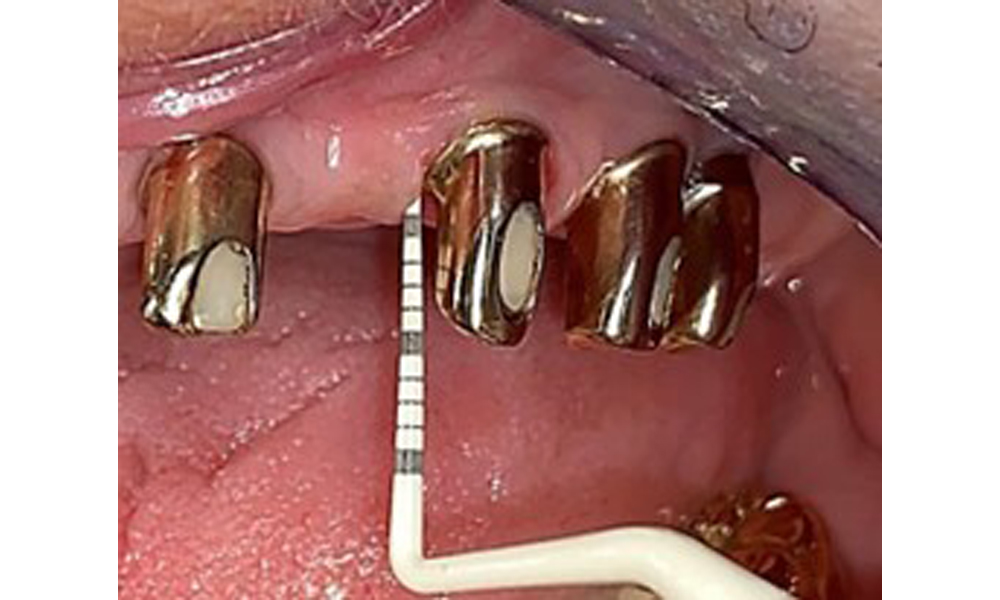

Occlusal view of the mandible.

Fig. 4: Occlusal view of the mandible.

The dental findings are as follows: Combined removable implant and tooth-supported telescopic prostheses on implants 15, 13, 21, 23, 24, 25 and tooth 11 (Fig. 1, Fig. 2, Fig. 3). The patient was fitted with a fixed mandibular denture. Adequate bridges were present over 37 to 34 and 45 to 47 (Fig. 4), the crown margins were intact and there were no active caries. A composite filling with a marginal gap was present on tooth 43. There was mandibular gingival recession, exposing 1 to 3 mm of root surface. This also applies to 11.

The radiological findings show partially edentulous dentition with maxillary implants for teeth 15, 13, 21, 23, 24, 25 and a telescopic crown on tooth 11. Adequate mandibular bridges spanning 37 to 34 and 45 to 47 are present. 48 is impacted. There are suspected secondary caries distally on 43 and mesially on 44. 44 is restored with a non-radiopaque cavity lining. There is generalised horizontal bone loss of approx. 10% to 30% and localised vertical bone loss affecting teeth 22 and 42 (Fig. 5).